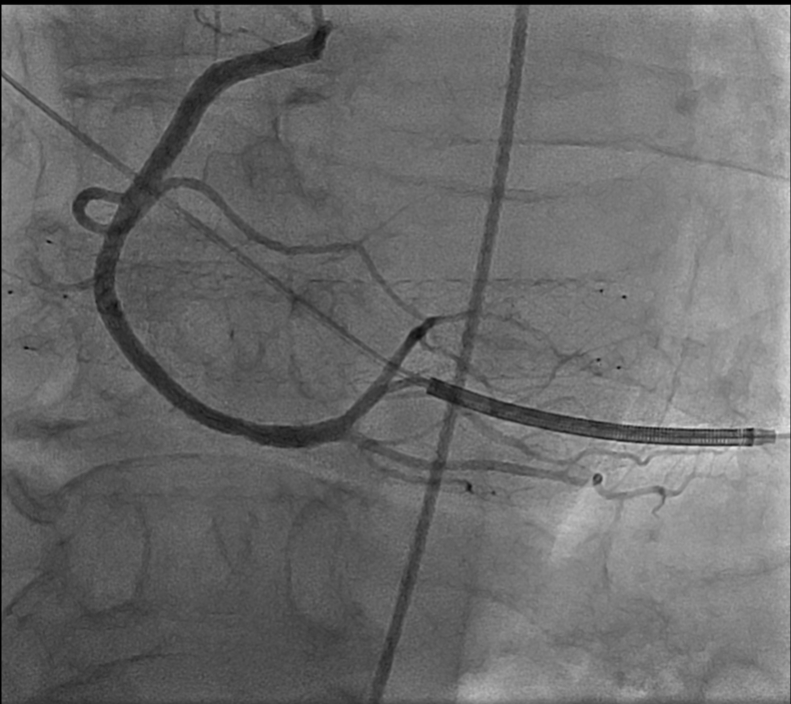

A 69-year-old male with extensive cardiac and peripheral vascular disease. Presented to our clinic with episodes of dizziness, dyspnea, and chest pain. Episodes occur during the day, relieved with rest. Examination was significant for systolic murmur, healed foot ulcer, moderate lower extremity swelling, and varicose veins. Patient has received a (16 x 100 Zilver venous stent) for severe stenosis in the left iliac vein in 3/2022. Transthoracic echocardiography showed an echodense tubular structure measuring 10 x 2 centimeters, resembling a stent, in the right atrium crossing the tricuspid valve into the right ventricle and holding the tricuspid valve open, causing severe TR. Cardiac catheterization was performed, confirming the stent position. The patient underwent surgical extraction of the stent and tricuspid valve repair.